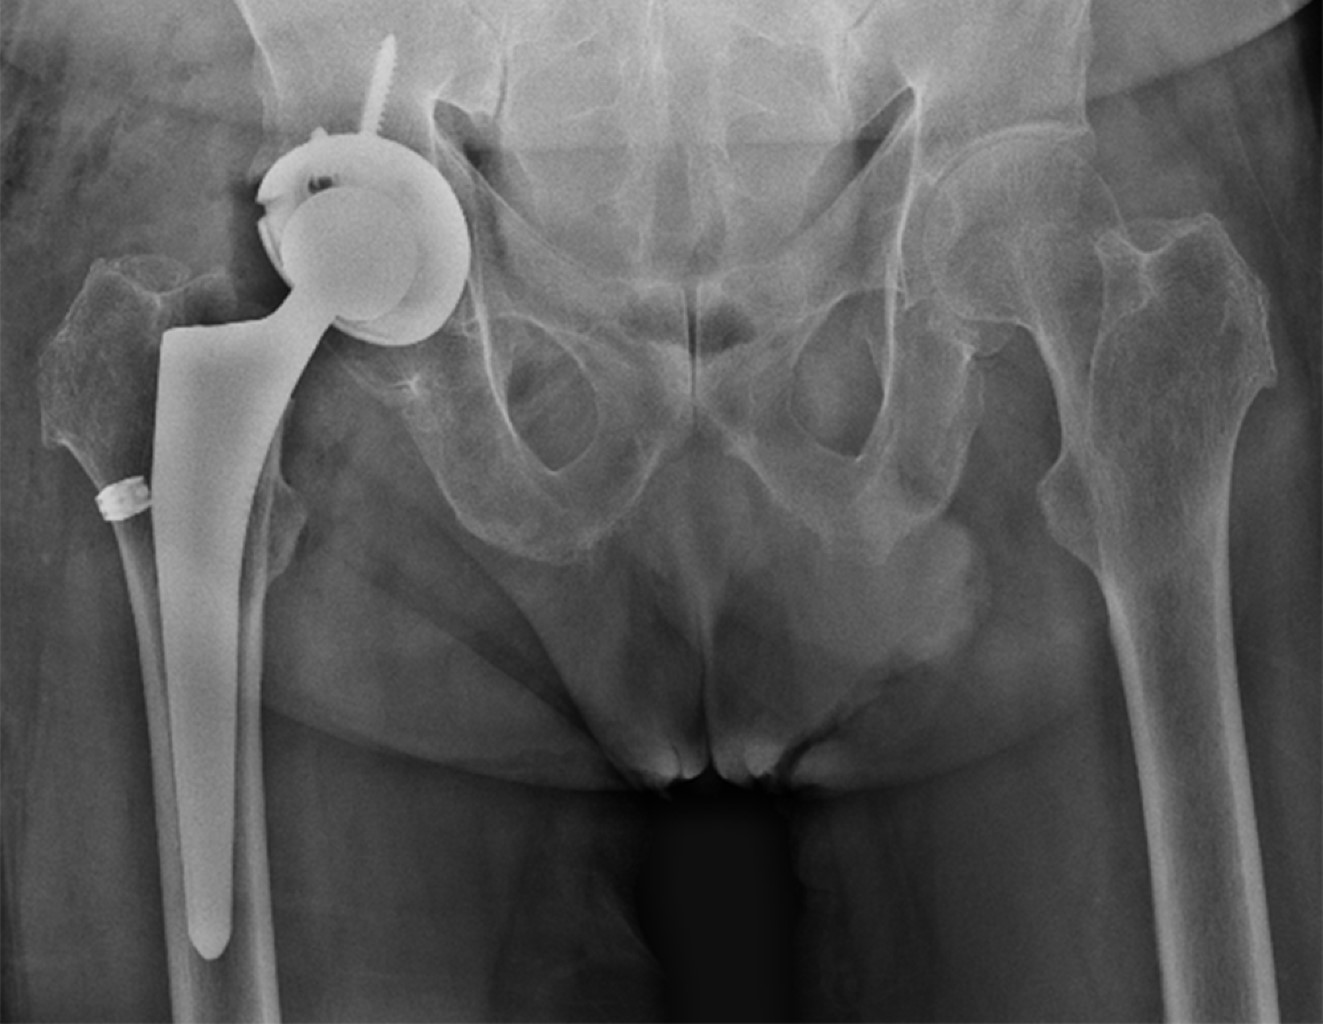

Alkaptonuria: evolution and course of the disease towards ochronotic arthropathy. Series of cases managed with joint replacement

Introduction: alkaptonuria is a very rare metabolic disease with autosomal recessive inheritance due to HGA oxidase deficiency. Classically described and diagnosed in the third to fourth decade of life, affecting both men and women; Its diagnostic impression is clinical based on the blue/black coloration of the conjunctivae, however it is confirmed by the specific analysis of the enzyme in the urine, to date there is no cure and its treatment is palliative and symptomatic. Material and methods: descriptive, observational, case series study, the primary objective of which is to describe the progression of the disease and its involvement in the musculoskeletal system. Results: two clinical cases are presented in women and men in which the broad clinic is illustrated, its progressive advance and the different alterations that it can generate in the musculoskeletal system. Conclusions: alkaptonuria is a rare disease which leads to a severe secondary arthropathy, currently without a specific management which is based on treating the symptoms, in its final stages joint replacements are a management option with satisfactory results for the relief of pain.

Figure 3